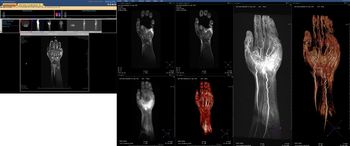

The exhibition booths occupied by vendors of ultrasound systems at ECR 2010 are likely to be very busy places throughout the congress. Difficult economic conditions are causing a dip in global demand for the more capital-intensive modalities like CT and MRI, and hospital managers are keen for their staff to explore the clinical potential of this versatile and cost-effective technology.